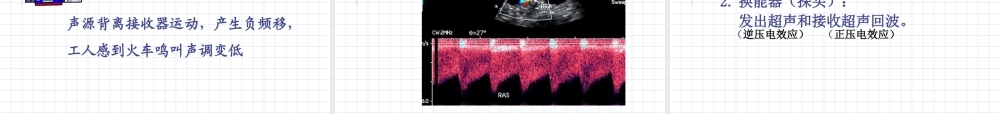

超声诊断广东省中医院影像教研室 超声诊断( ultrasonic diagnosis ) 是指运用超声波的原理对人体软组织的物理特性、形态结构与功能状态作出判断的一种非创伤性检查方法。 第一章 超声诊断基础知识 第一节 超声波与超声诊断原理 声波——物体的机械震动在介质(空气、水、固体等)的传播过程中产生的纵波称为声波。(机械波) 人耳听觉范围为 16-2 万 Hz (赫兹、赫)。超声波——声波频率超出人耳听力范围 2 万 Hz(赫)的高频声波称为超声波。目前应用于医学诊断超声波频率在 1-20 兆赫(MHz), 其中又以 2-14MHz 最为常用。 (二)超声波三个主要物理量:① 波长( λ ); ② 频率( f );③ 声速( c )。 声速(超声在介质中的传导速度,也可说超声在人体中传导的穿透力)与频率及波长有一定关系: c = f ·λ 一般超声波在固体中传播速度最快 > 软组织、液体 > 气体。例如:头颅骨 3360m/s> 人体软组织(体液、血液) 1540m/s > 空气 332m/s 。 频率越高,波长越短,穿透力越差,但分辨力越高,适合于浅表器官的探查。 频率越低,波长越长,分辨力越低,但穿透力越好 , 适合于心脏等深部脏器的探查。 根据公式: c = f ·λ 1. 方向性(束射性) 2. 反射、折射3. 衍射、散射 4. 吸收衰减特性5. 多普勒 ( Doppler ) 效应(三) 超声波的物理特性: 1. 方向性(束射性) 是超声对人体定向探测的基础。频率越高,方向性越好。 超声在介质中传播时,由于不同介质的声阻抗不同,界面大小不一,可发生反射、折射与衍射、散射。 回声反射的强弱由界面两侧介质的声阻抗差决定。 人体软组织声阻抗差异很小,只要有 1‰ 的声阻抗差,便可产生反射。 声阻抗( z )——指阻挡声波在介质中传播的阻力。公式: z = c · ρ c —— 声速 ρ—— 介质的密度可见声速越快,介质密度越高,声阻抗越大。 超声在固体中传播时声阻抗最大; 在软组织和液体中次之; 在气体中最小。超声在两种不同密度的物体中,由于声阻抗不同,形成界面。 大界面——界面尺寸大于波长 小界面——界面尺寸小于波长 2. 反射、折射 超声遇到大界面时产生反射和折射 。 声阻抗差越大,反射就越强,折射就越小。 反之,声阻抗差越小,折射就越强,反射就越小。 声波垂直入射和斜入射时反射和折射 反射:超声波在介质中传播时,遇到不同声阻抗的分界面且界面厚度远大于波...